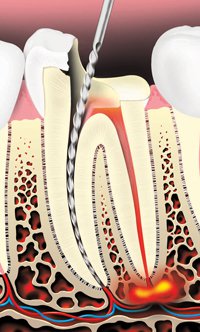

The decay is removed and an opening is made through the crown of the tooth into the pulp chamber.

The pulp is removed and the root canals are cleaned and shaped.

- First, your tooth is numbed for your comfort. A thin sheet of latex rubber is placed over your tooth to keep it dry. An opening is made through the crown of the tooth into the pulp chamber.

- The tooth’s nerve or pulp is removed from the pulp chamber and root canal (the space inside the root). Each root canal is cleaned and shaped so it can be filled.

- Your dentist may place medicine in the pulp chamber and root canal to help get

rid of bacteria. - The root canals are usually filled with a rubber-like material to seal them.